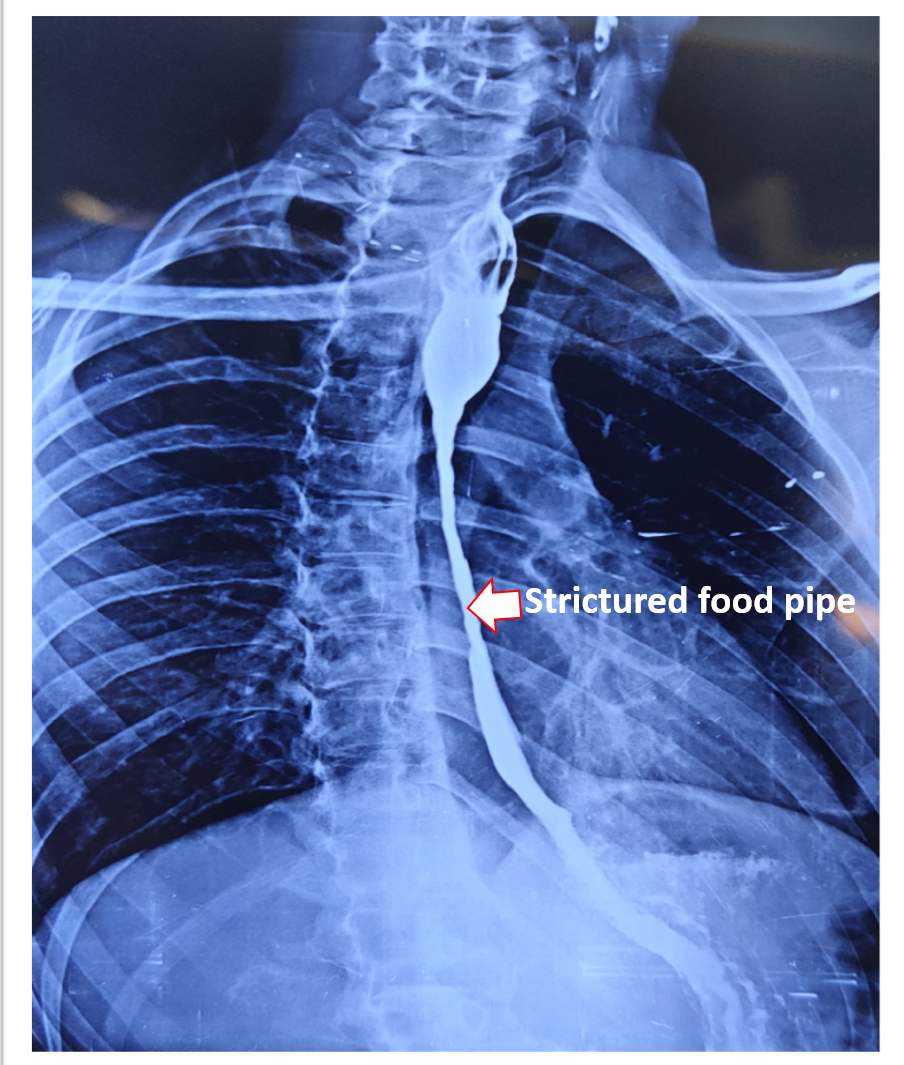

Life took terrible turn when a 27 years medical student ingested toilet cleaner with the intention to end it. Thou’ she could not succeed and by the time she realized, it left her with a strictured food pipe “Esophagus” and a scarred soul. Not able to eat came as a disastrous consequence despite multiple attempts at endoscopic dilatation of the food pipe stricture. With limited hope and debilitating health, she was referred for the possibilities to restore what she has lost so that at least she could resume eating.

It is not uncommon among young individuals to attempt on his or her own life when miseries take a toll on mind and soul. Ingestion of toilet cleaner which is a household commodity is one such common practice. It contains acid or alkali, ingesting which causes serious burn to the food pipe. Often patient survives the initial trauma to present later with stricture of the esophagus and total inability to eat to an extent they cannot event swallow his or her own saliva, crippling them mentally and nutritionally.

The treatment initially is to dilate the stricture with endoscope to restore eating which might be successful in some. Failing endoscopic dilatation or stricture which has ruptured during dilation need surgical replacement. Surgical replacement has evolved from using artificial pipes to bodies own organs suitable to restore the food pipe. The surgical principle is to identify the healthy upper part of esophagus which is in the neck, leave behind or remove the scarred esophagus, prepare the conduit (stomach tube, colon, jejunum) for replacement, transport it from abdomen to the neck under the chest bone (sternum) and join it to healthy esophagus in neck (Fig- 2/2p/3). The entire procedure involves three major compartments of human body, lasts from 4 to 8 hours, more than a week to recover from surgery and with known procedure related morbidity and mortality if not performed in a specialized centre. Patient are allowed to sip liquids from firs day to resume to normal diet may take a week but eventually they “EAT”